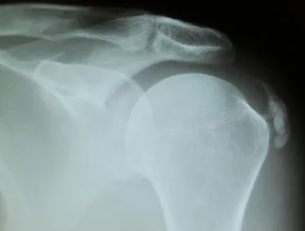

3. 어깨 석회질의 수술적 치료: 언제 필요할까?

비수술적 치료로 증상이 호전되지 않거나, 석회질 크기가 크고 통증이 극심할 경우 수술적 치료를 고려합니다.

- 관절경 수술:

- 작은 절개를 통해 카메라와 기구를 삽입하여 석회질 제거

- 회복이 빠르고, 주변 조직 손상이 적어 효과적

- 석회질 제거 수술:

- 석회가 너무 크거나 관절경으로 제거가 어려운 경우 시행